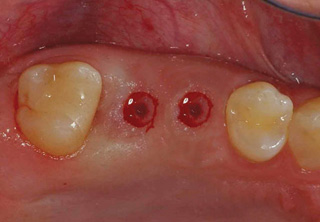

컴퓨터 분석을 이용한 임플란트

흔히 "네비게이션 임플란트"라고 말하는 컴퓨터 분석을 이용한 임플란트란?

컴퓨터 분석을 이용한 임플란트는 3차원 영상 분석을 통하여 적절한

임플란트의 식립 위치와 방향 등을 결정하여 치료계획을 수립하고,

이를 토대로 개별 맞춤 수술유도장치를 제작하여 시술하는 방법입니다.

일반적으로 잇몸을 절개하지 않고 시술하여 수술시간이 짧으며, 수술 후 통증이나 붓기, 출혈이 적은 장점이 있습니다.

3D 모의시술로 식립

시술 전 3D영상장치 등을 통한 진단계획과

모의 수술을 통해 환자의 골조직과 신경관의

위치 등을 파악하여 명확한 치료 계획을

수립하고 개별 맞춤 수술유도장치를

사용하므로 신경 손상 및 부정확한 임플란트

시술의 위험이 적습니다.

무절개 시술로 빠른 회복

무절개 시술이므로 일반 절개 시술에 비해

붓기와 출혈이 적어 염증 및 감염의 위험이

낮고 빠른 회복이 가능합니다.